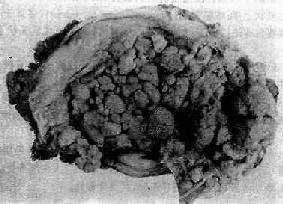

肉眼观,肌瘤可以生长在子宫任何部位,常位于子宫壁内(肌层内肌瘤)、浆膜下(浆膜下肌瘤)或粘膜下(粘膜下肌瘤)。可单发或多发,常为多个,其数目多少不等,常见为数个、乃至十数个或数十个,称多发性平滑肌瘤。肌瘤的大小可极为悬殊,小的在显微镜下才可检见,大的如成人拳大或更大,甚至可充满整个腹腔。肌瘤多呈球形或融合成不规则形,质较硬,界限明显,但无明显包膜(图13-7)。切面上,瘤组织常呈灰白色,编织状或旋涡状,当肌瘤生长较快或供血不足时,可发生各种继发性改变,如玻璃样变、粘液变、囊性变、水肿及出血、坏死等。

图13-7 子宫平滑肌瘤

多个肌瘤结节,位于肌壁内、粘膜下及浆膜下,境界分明,宫腔受挤压呈裂隙状